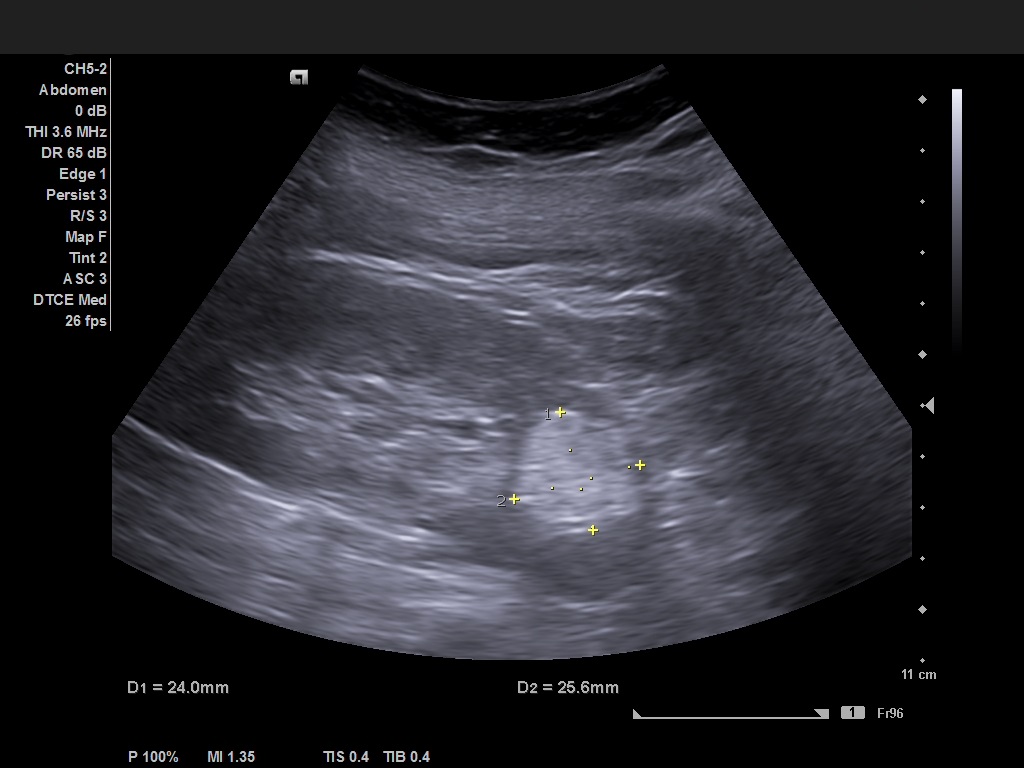

A 66 yo female with a history of painless, gross hematuria for several months has the following US image. She had no other lower urinary tract symptoms, no history of fever, weight loss, renal stones disease or trauma. What is your diagnosis?

Case courtesy of Prof Adrian Saftoiu